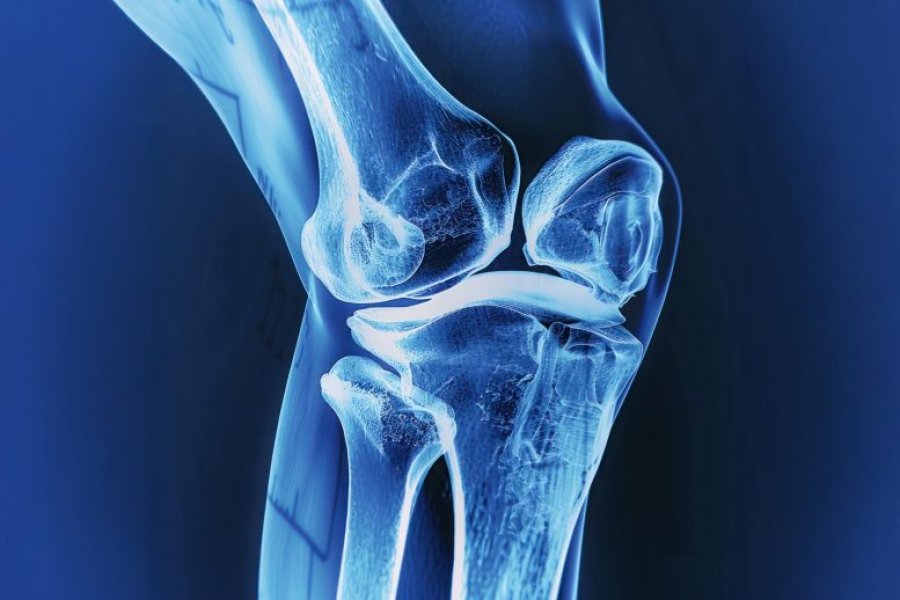

Shpesh kockat e thyera shërohen vetë, por në rastet e frakturave shumë të rënda ose kur hiqet një tumor në kockë, mjekët vendosin implante për të stabilizuar zonën dhe për të ndihmuar rikuperimin. Sot këto implante zakonisht bëhen nga kocka e vetë pacientit ose nga metale dhe qeramika. Megjithatë, përdorimi i kockës së pacientit kërkon një operacion të dytë, ndërsa implantet metalike janë më të forta se kocka natyrale dhe mund të lirohen me kalimin e kohës.

Kur një kockë thyhet, trupi krijon fillimisht një strukturë të butë në vendin e dëmtimit që lejon qelizat dhe lëndët ushqyese të depërtojnë në zonë. Me kalimin e kohës kjo strukturë zëvendësohet nga kocka e fortë. Hidroxheli i ri synon të kopjojë pikërisht këtë proces.